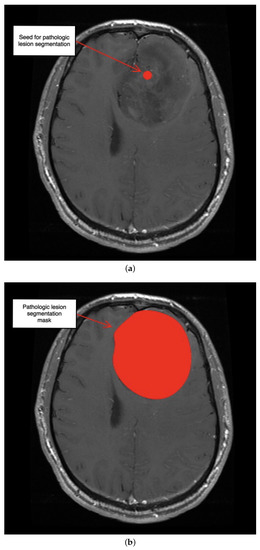

3.2. Second Scenario